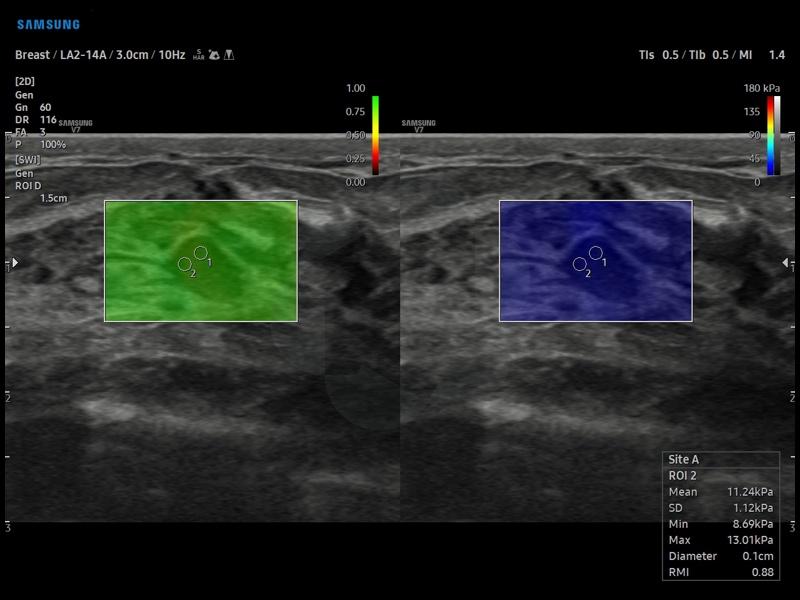

Функция S-Shearwave Imaging™ предназначена для неинвазивного анализа жесткости тканей при исследованиях различных анатомических структур. Провести диагностику с максимальной точностью помогут эластограмма с цветовой кодировкой, количественные измерения, различные параметры отображения и функции для работы с выбранной пользователем областью интереса.

Режим S-Shearwave - молочная железа